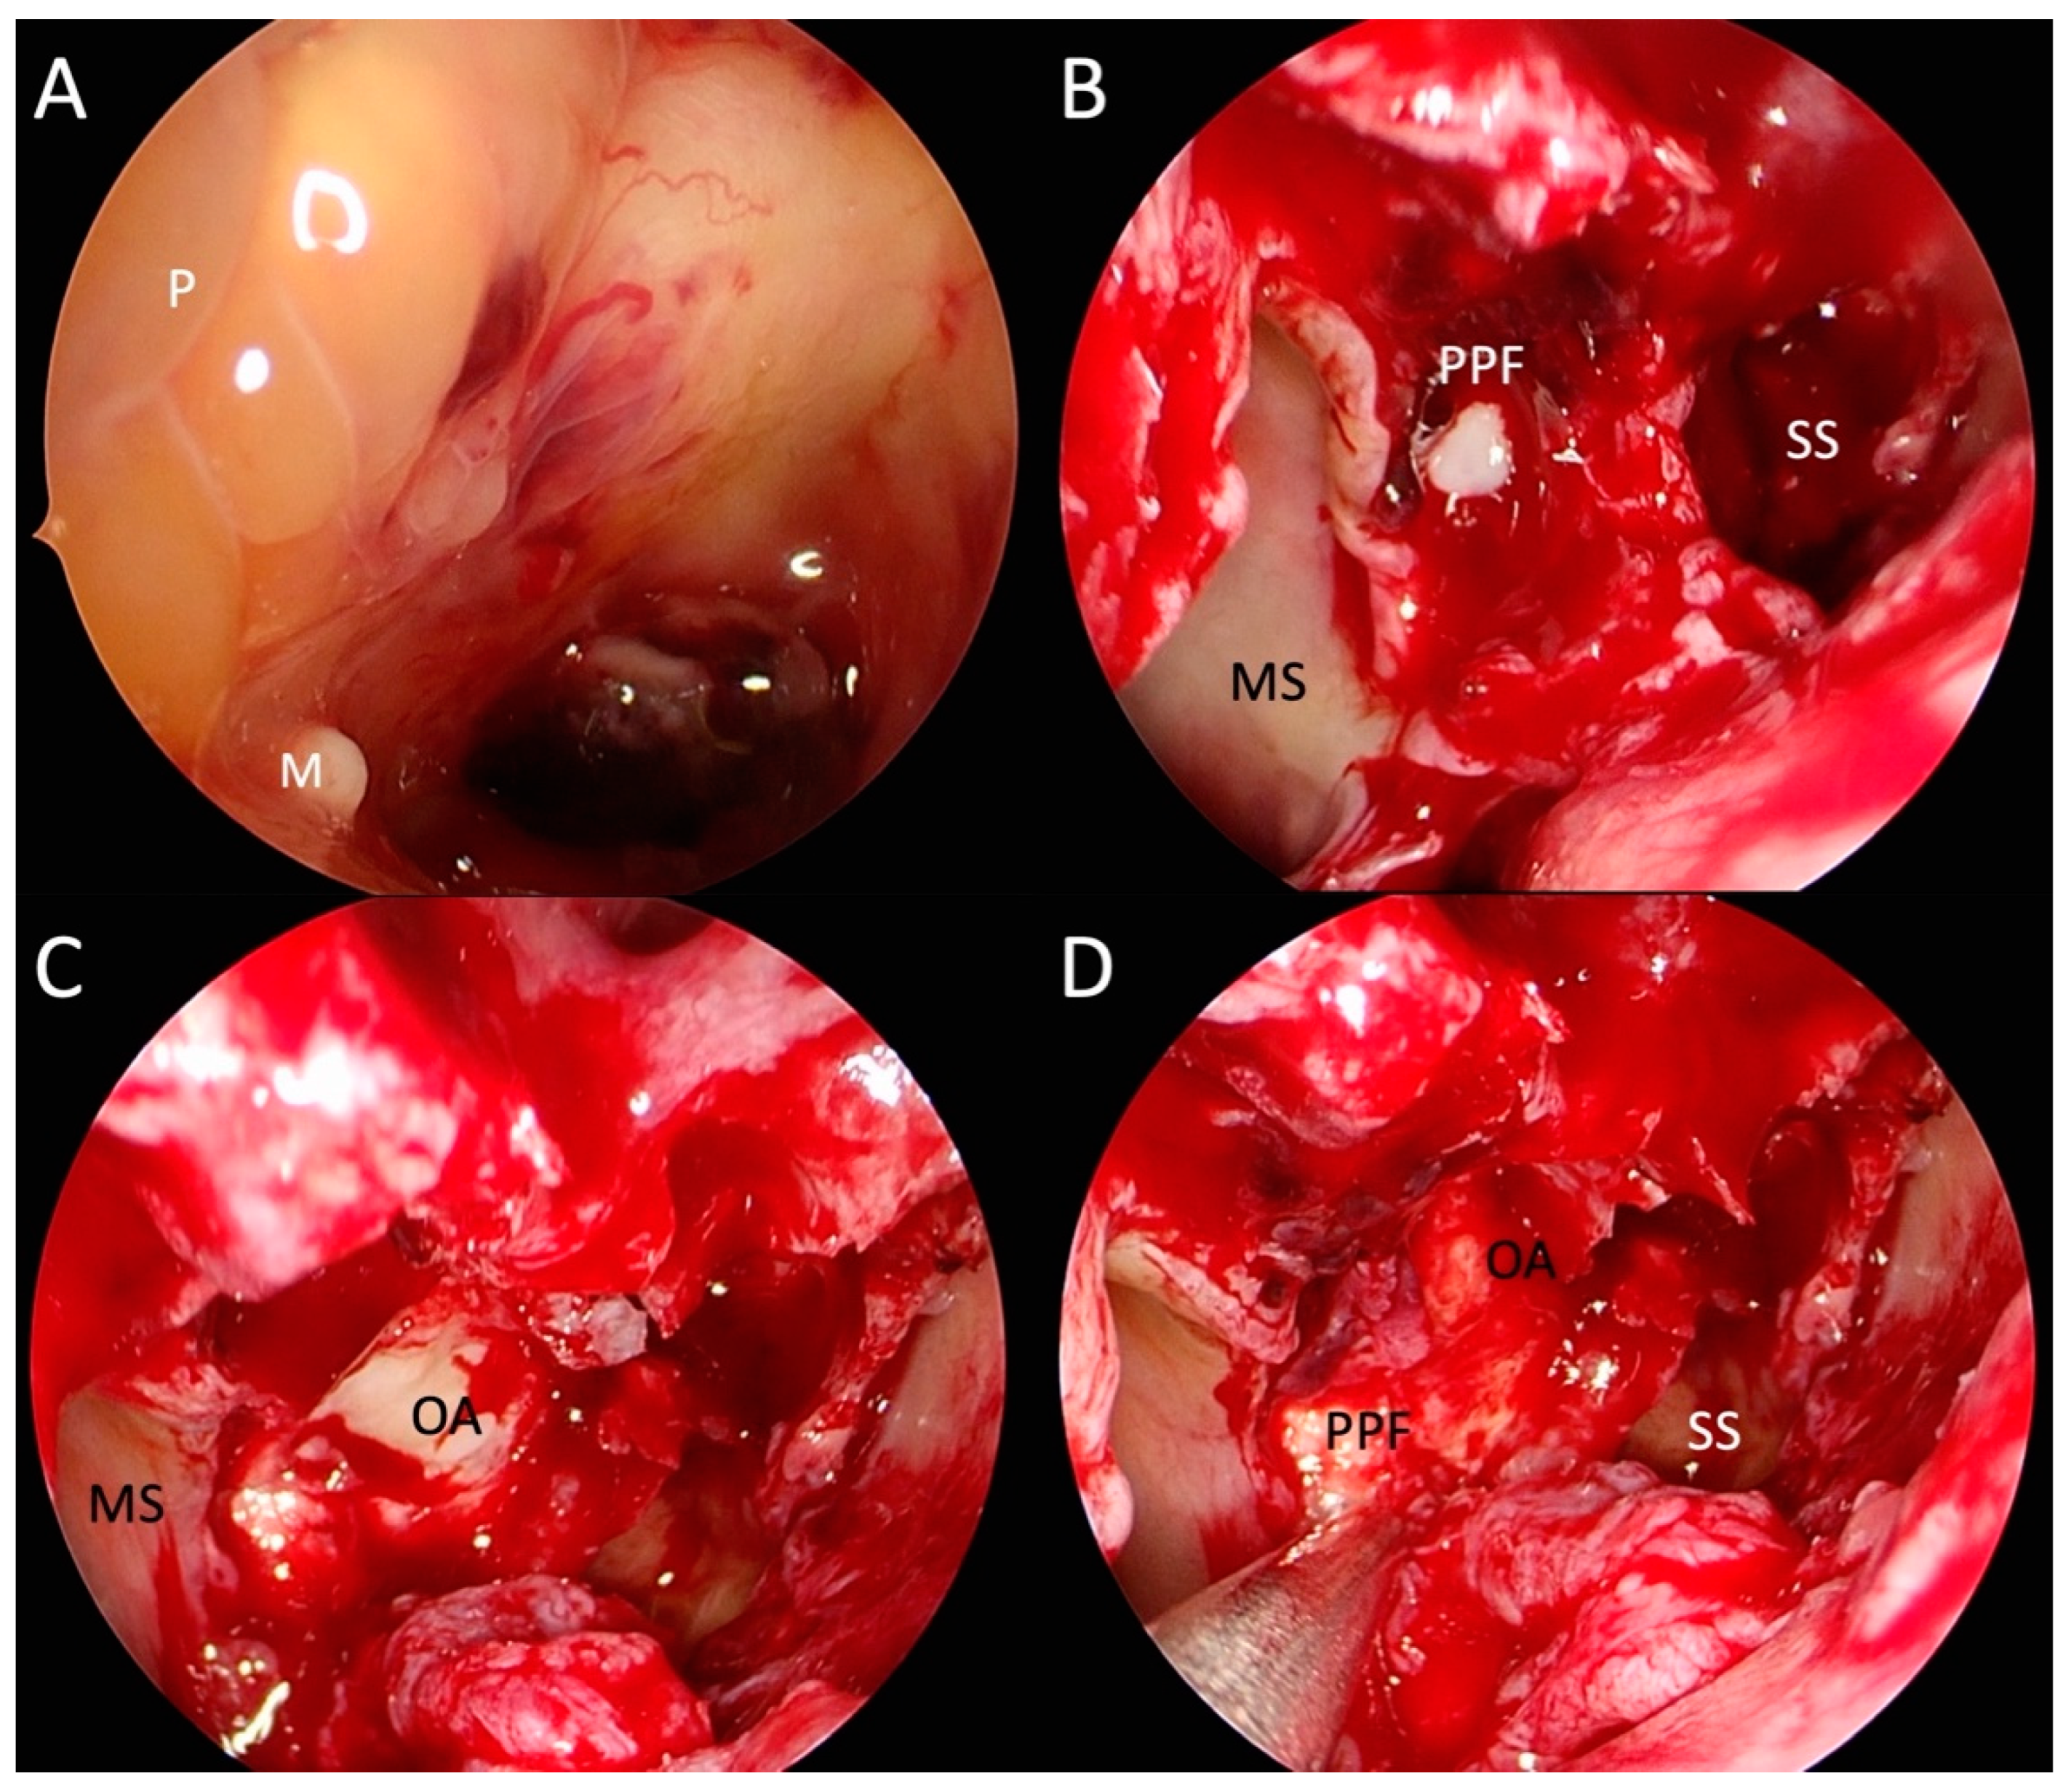

2. Case Presentation

2.2. Revisional Treatment